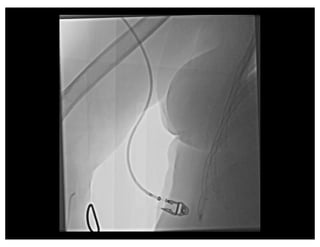

Negotiating Subclavian Tortuosity

Effect of Inspiration

Panel A: During expiration there is a more acute angle (α) between the brachiocephalic

trunk and the ascending aorta, therefore the wire takes a more horizontal a more horizontal

direction towards the descending aorta. Panel B: During deep inspiration, the diaphragm

lowers the heart and straightens the angle (α) between the brachiocephalic trunk and the

ascending aorta. The wire takes a more vertical direction towards the ascending aorta.